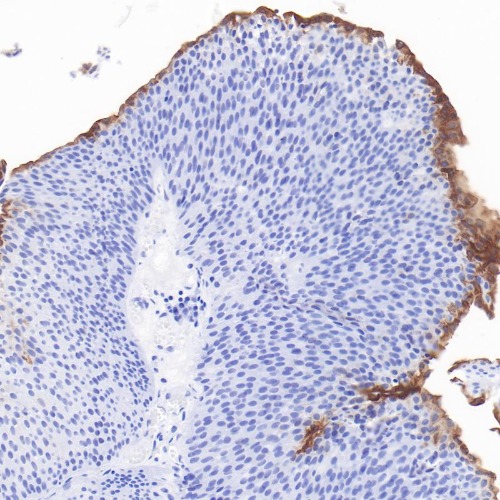

Immunohistochemical staining of urothelial carcinoma tissue using Uroplakin II Monoclonal Antibody(ARB600)